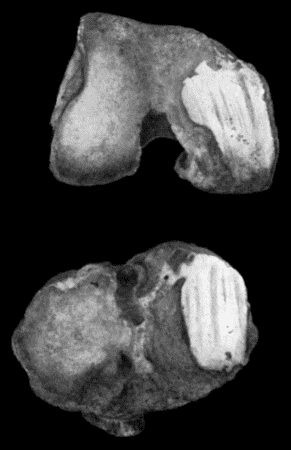

530 162.Bones of Knee in Charcot's Disease

533 163.Charcot's Disease of Left Knee